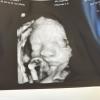

Девочки, подскажите, кто делал 3Д узи, на каком сроке и нужная вещь вообще?

У меня сейчас 31 неделя и думают стоит ли, так как везде написано до 28 недели нужно делать.

Может кто-то делал на более позднем сроке?

В 24 недели делала но малышка закрылась фото на память не получилось. И делала в 33 недели хороший снимок.

Делают для себя, чтобы фоточки лица сделать) Я делала на 26. На вашем сроке может просто ребенок не «влезть» в кадр 😂